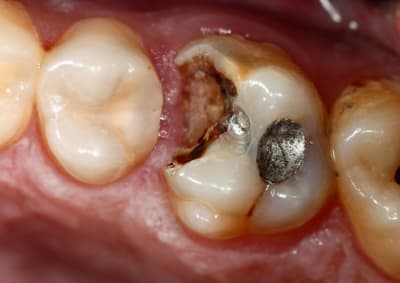

Si dés le départ on décide de faire l'endo et couronne, on taille, on ouvre, et a la fin on se dit qu'on a bien fait de faire la couronne, vu qu'il reste pas grand chose. Au passage on perd beaucoup de résistance mécanique de la dent, et on descend toute les limites au niveau gingival ce qui dans le temps expose la limite à une contamination biologique, reprise de carie ...etc...

1) Preventing contamination of the root canal between the root treatment (l'endo) and placement of restoration is extremely important. Contamination is considered a major cause of failure of root treated teeth (endo). Therefore the tooth should be restored immediately after endo i.e. dans la meme sceance.

2) Un des problem avec the pose d'un inlay-core est de protéger la canal entre RVs. Un couronne provisoire ne protege pas du tout la dent contre contamination bactérienne et pas plus que si la dent est laissé ouvert.

3) La raison d'être d'un tenon est de retenir un core a cause d'un gross perde de matière dentaire.

CA NE RENFORCE PAS LA DENT et peut meme la rendre plus fragile. Les dentistes devrait éviter d'utiliser un tenon/inlay-core quand il existe des traits anatomique pour retenir un core de matière.

4) Les inlay-cores coulé ne fonction pas aussi bien que d'autre tenons et il y a la problem de temporisation de la dent. Pour ces raisons il ne sont que très peu utilisé (dans la monde entier!).